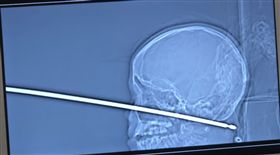

跌下樹遭烤肉叉刺穿頭 童這麼做保命

美國密蘇里州哈里森維爾(Harrisonville,...